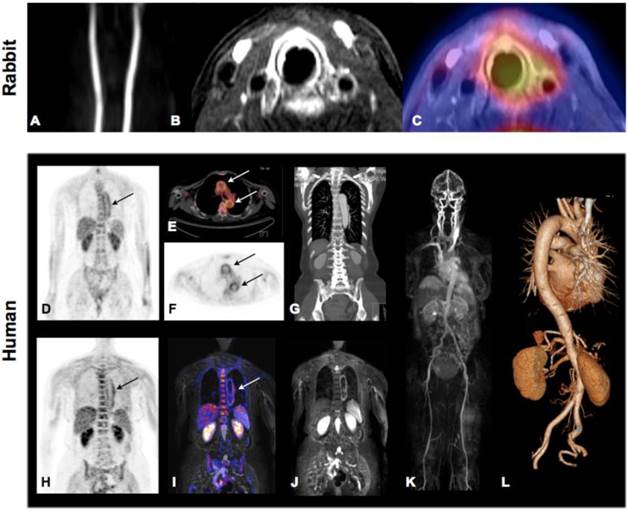

Novel hybrid imaging technologies will be helpful in correlating specific tracer accumulation within the vessel wall/atherosclerotic lesions and lesion morphology when imaged simultaneously by CT or MRI. Figure 5 shows successful 18F-FDG imaging of plaque inflammation in a hypercholesterolemic rabbit by full hybrid MR-PET (Panel A-C) as well as vessel wall inflammation in a patient with large-vessel vasculitis by both PET-CT and MR-PET (Panel D-L). PET-MR may in particular be promising for detection of vulnerable plaques as it combines the molecular information reported by various tracers from the PET with high-resolution and functional imaging by MRI.

Fig 5

Molecular Imaging of atherosclerosis by hybrid PET-CT and MR-PET. Inflammation in plaques of hypercholesterolemic rabbits can be assessed and quantified by 18F-FDG PET and co-localized to carotid artery by simultaneously acquired MRI. Panel A: TOF angiography, Panel B, contrast enhanced fat-suppressed T1 weighted MRI (delayed enhancement), Panel C: MR-PET fusion showing increase tracer accumulation around the left carotid artery. Images demonstrate good correlation of PET signal and contrast-enhanced MRI but also show limited spatial resolution of PET technology. Hybrid Molecular Imaging in a patient with large-vessel vasculitis (Panels D-L). Increased 18F-FDG uptake can be visualized by whole-body PET and correctly co-localized to the aortic arch by the subsequently performed contrasted enhanced CT (Panels D-G: PET-CT). Similar co-localization can be performed using hybrid MR-PET (Panels H-J). Whole body MRA (Panel K) and CTA (Panel L) can be routinely performed during hybrid image acquisition. Images courtesy of Isabel Dregely, Stefan Nekolla and Ambros J. Beer from the Munich PET/MR consortium of TUM and LMU (funded by DFG).